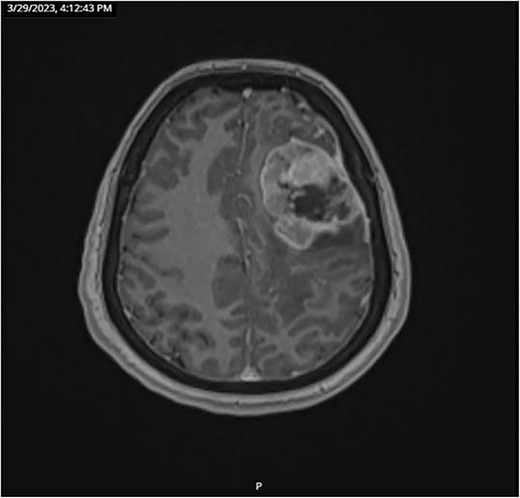

A 59-year-old female patient, married with no offspring. Surgical history includes cholecystectomy (2017). Her brother died due to lymphoma; otherwise, there is no family history of cancer. She presented complaining of chronic constipation, weight loss, abdominal distention, and perianal pain. Colonoscopy revealed a 5-cm mass extended from the anus. Biopsy revealed invasive, moderately differentiated rectal adenocarcinoma (Fig. 1).

Microscopic view (×10) of pathology slide of colorectal cancer.